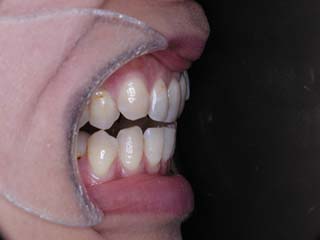

主訴:前歯の噛み合わせ

診断名:叢生を伴う開咬

本症例について検査診断の結果、開咬、叢生、下顎前突傾向を認めました。患者希望を考慮し、治療メカニクスとして、非抜歯配列、上顎のみリンガルブラケット矯正装置、下顎唇側マルチブラケット矯正装置、および、目的外使用のオーソアンカー SMAPシステムを用いることにいたしました。

リンガルブラケットで有れば、内側に歯科矯正用アンカースクリューを装着する方が楽なのですが、この当時は歯科矯正用アンカースクリューの成功率が十分ではない感触があったので、オーソアンカー SMAPシステムを第一選択肢にしていました。今は逆です。場所さえ選べば、歯科矯正用アンカースクリューの成績は決して悪くない上に、装着時の疼痛が極めて少ないことから、第一選択肢を歯科矯正用アンカースクリューにする事が多くなりました。